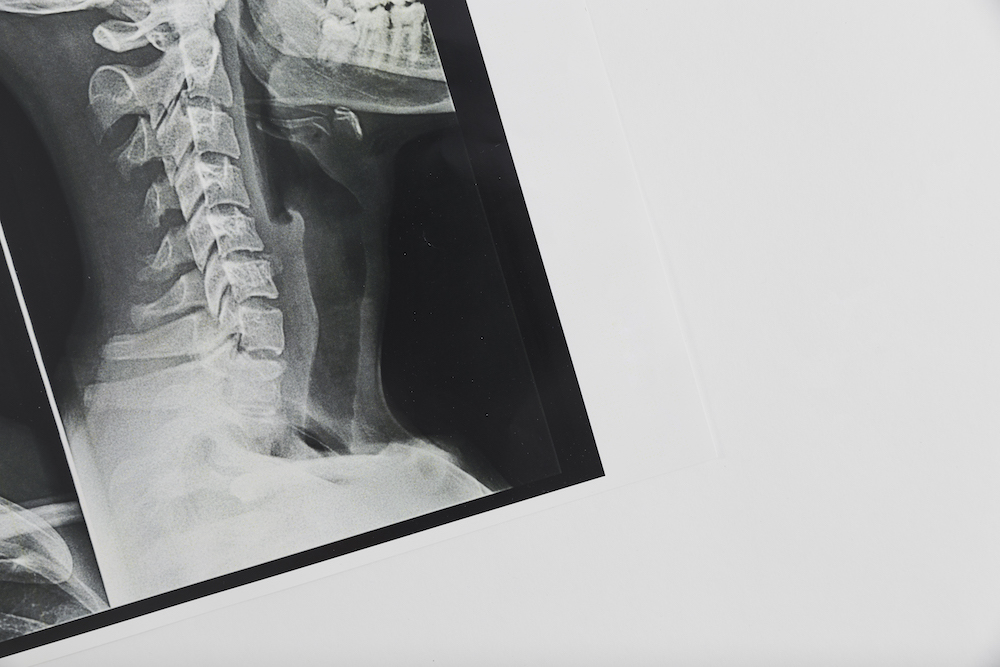

Spine X-Ray in Sarasota

Spinal X-Rays in Sarasota

Getting an X-Ray of Your Spine

Getting an x-ray of your spine gives us an extremely detailed look at what’s going on with your spine. Many times, this can help us confirm the diagnosis and give us confidence in the right treatment plan to help getting you back to optimal health.

If you’ve been experiencing back pain, neck pain, or headaches, or other discomforts, a spinal x-ray can help us identify the cause and give us a clear path for treatment.

A spinal x-ray can give Dr. Hornberger important information about your spine. The imaging can help diagnose problems with your bones, joints, and discs. A spinal x-ray can also help find problems with the ligaments, muscles, and other soft tissues in your back that are tougher to diagnose without the images. Measurements are made of the images detailing the position and extent misalignments thus aiding in the spinal correction process.